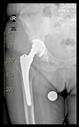

The radiological examination allowed us to verify the close bone-to-implant contact and the unchanged position of the implant during follow-up.

In all the cases operated with the above-described targeting procedure, the stems of the cups remained between the cortical bone surfaces without perforation of the linea terminalis, as shown by postoperative radiographs. There were no complicated surgical situations. In 16 cases, the wound healings were uneventful, and the hips were able to bear weight again after postoperative rehabilitation.